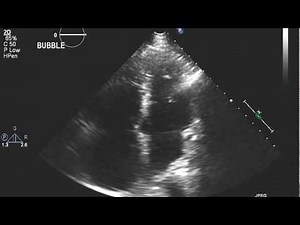

9 Steps to Perform an Echo Bubble Study

Step-by-step bubble study procedure and echo protocol for accurate detection of right-to-left shunts using agitated saline contrast.

7 Indications for an Echo Bubble Study

Bubble Study On Transesophageal Echocardiography | RK.MD

Bubble Study Technique

ECHO bubble test. Heart is shown upside down and the left side of s

Echocardiogram with Bubble Study: Extracardiac Shunt

Bubble test echocardiography - transthoracal and transesophageal

Understanding Bubble Study in Cardiac Assessment

Bubble contrast echocardiography

Shunts & Bubble Studies - Alberta Sono